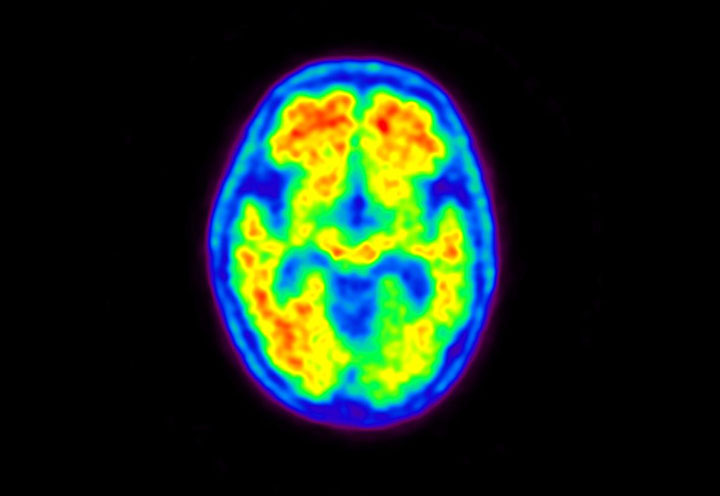

Head / Case5 : Amyloid

Courtesy : Kindai University Hospital

- Imaging protocol

- Injected dose: 4.27 MBq/kg, 18F-Flutemetamol

- Uptake time: 99 minutes

- Scan time: 20 minutes